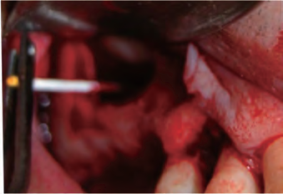

在上颌窦粘膜提升过程中,使用棉拭子从上颌窦底采集样本,并接种培养以确定是否存在细菌(图1)。若样本无细菌检出或者培养结果显示为多微生物污染,则弃置该样本。样本被送往实验室(Centro Analıtico Pozuelo, Pozuelo de Alarcon, Madrid, Spain)接种血平板培养和巧克力平板培养基37℃ 48小时培养,以进行微生物分析。为了获得可靠的比较结果,细菌被分为以下四类 :

图1. 上颌窦黏膜提升术中样本采集的临床图片